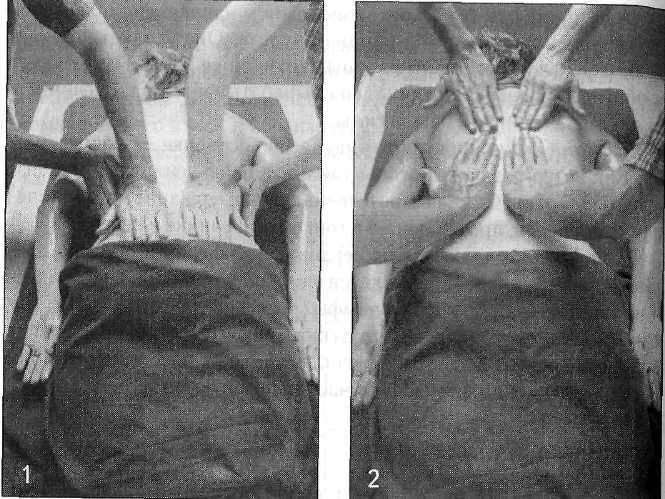

Бахья снехана представляет собой последовательность массажных движений, выполняемых в следующих направлениях: от пупка к голове, от головы к пупку, от пупка к ногам и от ног к пупку — на передней и задней поверхностях тела. Давление, прилагаемое массажистом, различается в зависимости от массируемой области (присутствия точек мармы). Согласно аюрведе, в точках мармы происходит соединение между физической материей тела и его внутренней мудростью. Стимуляция мармы оживляет и координирует взаимодействие субдош ваты, а следовательно, гармонизирует все нейрофизиологические процессы в организме.

Давление при массаже также увеличивает количество теплого кунжутного масла, проникающего в поры кожи. Обычно мы не думаем о коже как о поглощающем органе, хотя она может впитать действительно большое количество масла. Так же как и в других процедурах панчакармы, травяные масла выбираются с учетом конституции пациента.

Массаж и травы позволяют маслу проникать глубоко в ткани и разрыхлять «укладку» амы в этих тканях, в том числе на стенках шрот. Помимо этого, снехана увеличивает гибкость тела, увеличивает силу, уменьшает стресс и питает ткани. Слово «снехана» буквально означает «доброта, нежность, любовь», и эта приятная процедура оправдывает свое название.